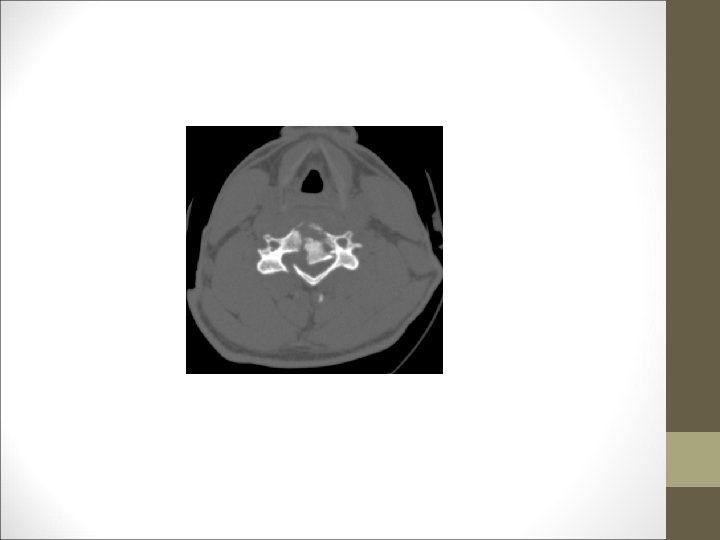

FACULTAD DE MEDICINA DEPARTAMENTO DE CIRUGÍA NEUROCIRUGÍA ¿Qué harías? TAC Cervical

TC Desplazamientos de fragmentos óseos ¿Algo mas? Desplazamientos discales y lesiones ligamentosa FACULTAD DE MEDICINA DEPARTAMENTO DE CIRUGÍA NEUROCIRUGÍA RM